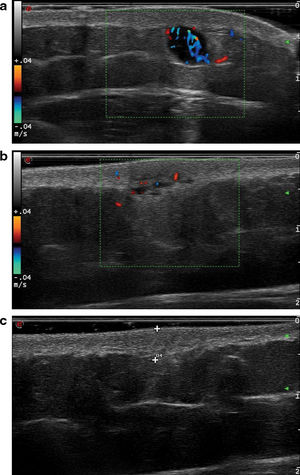

Ultrasound examinations were performed using an 18MHz probe on the Esaote Mylab™ Class C ultrasound machine. The findings are shown in Table 1. We categorized the lesions into 3 ultrasonographic patterns. Nodular pattern (3/10) included rounded lesions with well-demarcated borders and hypoechoic characteristics (Fig. 1a). Pseudonodular pattern (6/10) consisted of polylobulated lesions with poorly defined borders and heterogeneous echogenicity (Fig. 1b). The remaining lesion—showing a diffuse pattern (1/10)—was isoechoic, with poorly defined borders and a diffuse morphology (Fig. 1c).

(a) Ultrasound corresponding to lesion #2, showing a hypoechoic, rounded lesion with well-demarcated borders, following a nodular pattern. Posterior enhancement and significant vascularization are also observed. (b) Ultrasound of lesion #4. In this case, a heteroechoic, polylobulated lesion with poorly defined borders, characteristic of the pseudonodular pattern, is seen. Vascularization is present but less profuse vs the previous case. (c) Ultrasound of lesion #10. This is an isoechoic, poorly defined lesion following a diffuse pattern.